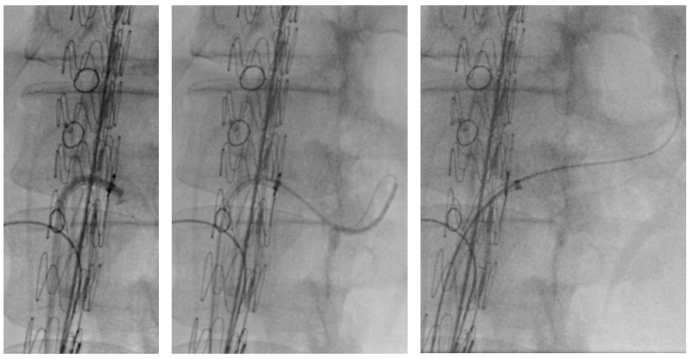

★ 标准化操作技巧

精确定位: 在X光下旋转主体支架,结合CA/SMA切线位造影,确保四个开窗/分支精确对准目标血管。

全程束径: 支架主体在体内需保持“束径”状态(即未完全释放),以维持其可转动性,这是超选成功的关键。

导管先行: 超选进入分支后,先置入导管而非硬导丝。硬导丝会将支架与分支“刚性”固定,丧失调整能力。待四个分支均被导管标记后,再逐一交换为硬导丝,此时支架位置已基本锁定,稳定性极佳。

球囊固定与释放: 四分支均植入球囊并充盈固定后,再释放主体支架的束径装置,完成最终释放,最后植入桥接支架。